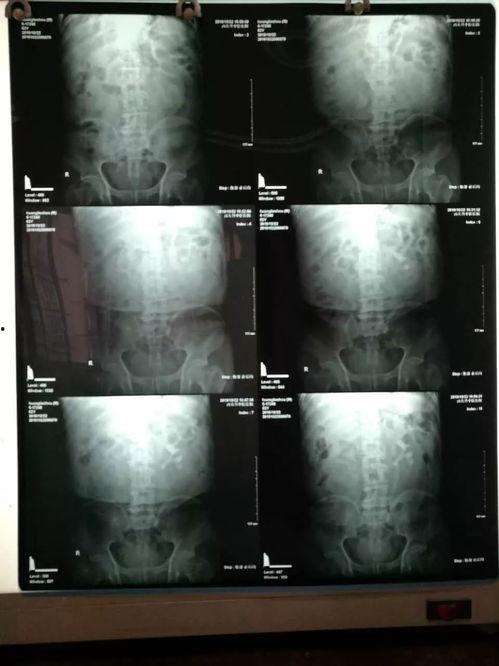

为了让大家更直观地了解激光碎石术,我们找到了一段精彩的激光碎石视频。在这段视频中,你可以看到医生如何将激光导入人体,精确地击碎结石。

在视频的开头,我们可以看到医生正在为患者进行手术前的准备工作。这包括对患者进行全身麻醉、消毒、铺巾等。一切准备就绪后,手术正式开始。

手术中段,医生将一根细长的导管插入患者的尿道,导管前端装有激光发射器。医生通过观察屏幕,精确地将激光导入结石所在的位置。

随着激光的发射,结石开始逐渐被击碎。你可以看到,原本坚硬的结石在激光的照射下,变得支离破碎。这一过程非常神奇,让人不禁感叹科技的伟大。

在激光碎石术的最后阶段,医生会继续观察结石的碎裂情况。当结石完全碎裂后,它们会随着尿液排出体外。这时,手术宣告成功。